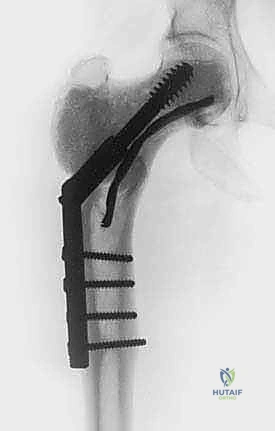

- الاستئصال الواسع (Wide Resection): إزالة الورم مع جزء كبير من العظم السليم المحيط به. يُستخدم للأورام الخبيثة.

- الاستئصال بالتبريد (Cryosurgical Ablation): الحل السحري الذي يجمع بين ميزة الحفاظ على العظم (مثل الكشط) وقوة تدمير الخلايا (مثل الاستئصال الواسع).

| الحفاظ على العظم والمفصل | ممتاز | ممتاز | ضعيف (يتطلب استبدال المفصل أو ترقيع واسع) |

| فترة التعافي والتأهيل | سريعة | سريعة إلى متوسطة | طويلة جداً ومعقدة |

| التأثير الوظيفي المستقبلي | طبيعي | طبيعي في الغالب | قد يصاحبه إعاقة حركية نسبية |